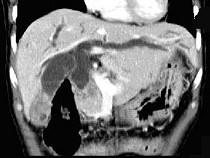

问题 患者,男,51岁,右上腹隐痛2月余,CT扫描如图,最可能的诊断是 ( )

选项 A.胆囊癌伴肝门胰头周围转移 B.胆囊息肉 C.胆囊黄色肉芽肿 D.慢性胰腺炎并胆囊息肉 E.胆囊腺瘤及慢性胰腺炎

答案 A